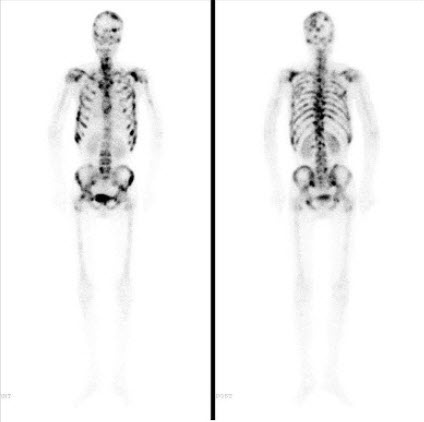

男,32岁,双侧上肢疼痛3个月,有慢性肾炎病史,无发热、无外伤及肿瘤病史,行全身骨显像如图,最可能的诊断是()

A.骨纤维结构不良

B.肾性骨营养不良

C.Paget病

D.双侧上肢骨转移癌

E.以上都不是